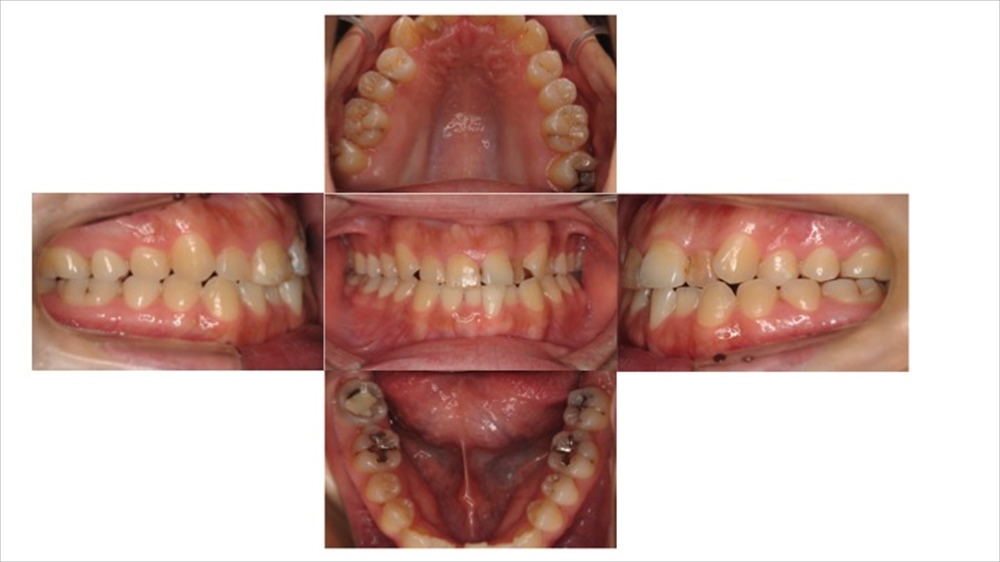

実際の練習風景になります。

撮影者によってズレがない様に私達は日々練習を行っています!!

上記の写真が練習によって精度が向上したお口の撮影になります。

ぱっと見わかりませんが、5枚ある写真の内右手の写真に違いがございます。

違う点としては“平行に確認しやすいように撮影できているかどうか”という点になります。是非、見比べてみてください。